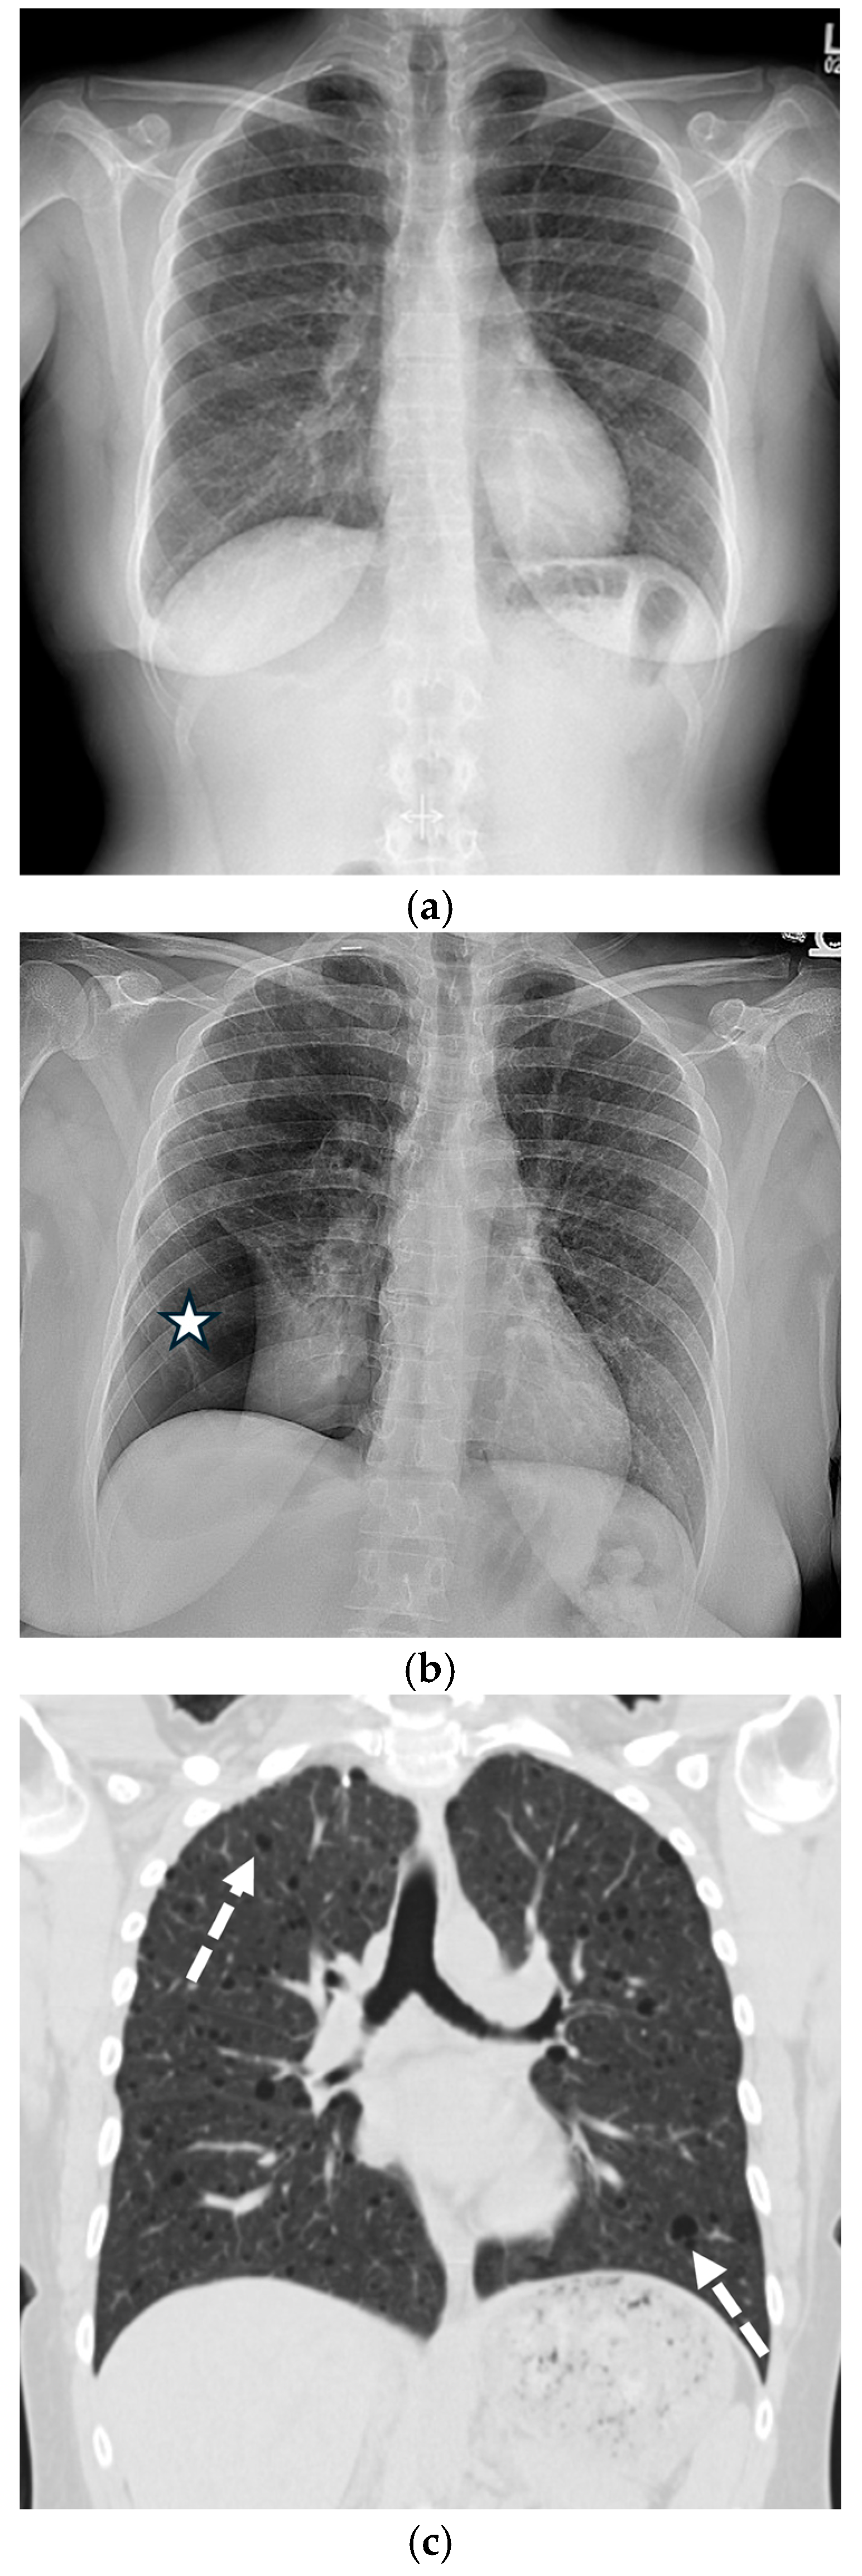

3.1. Chest Radiography

4.1. Chest Radiography Pitfalls

5.1.2. COVID-19 Pneumonia

5.1.3. Pneumocystis jirovecii Pneumonia (PJP)